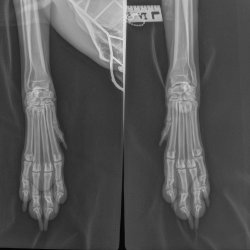

RTG snímek Rocky